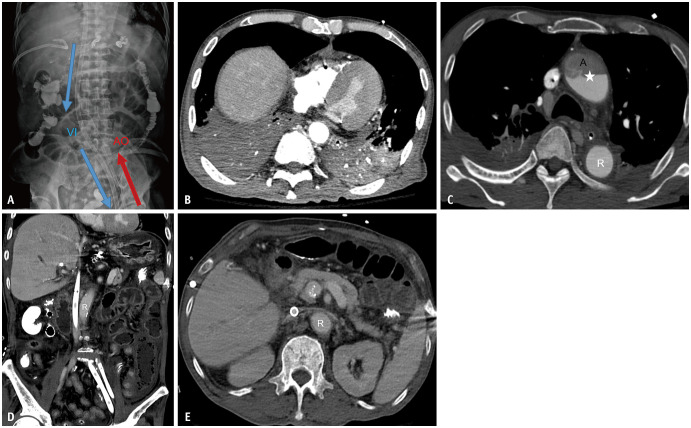

Contrast-Enhanced Abdominopelvic CT After Peripheral Venoarterial Extracorporeal Membrane Oxygenation.

Korean Journal of Radiology Pub Date : 2025-07-01 Epub Date: 2025-06-10 DOI:10.3348/kjr.2025.0256

Eun Sun Choi, Jong Keon Jang